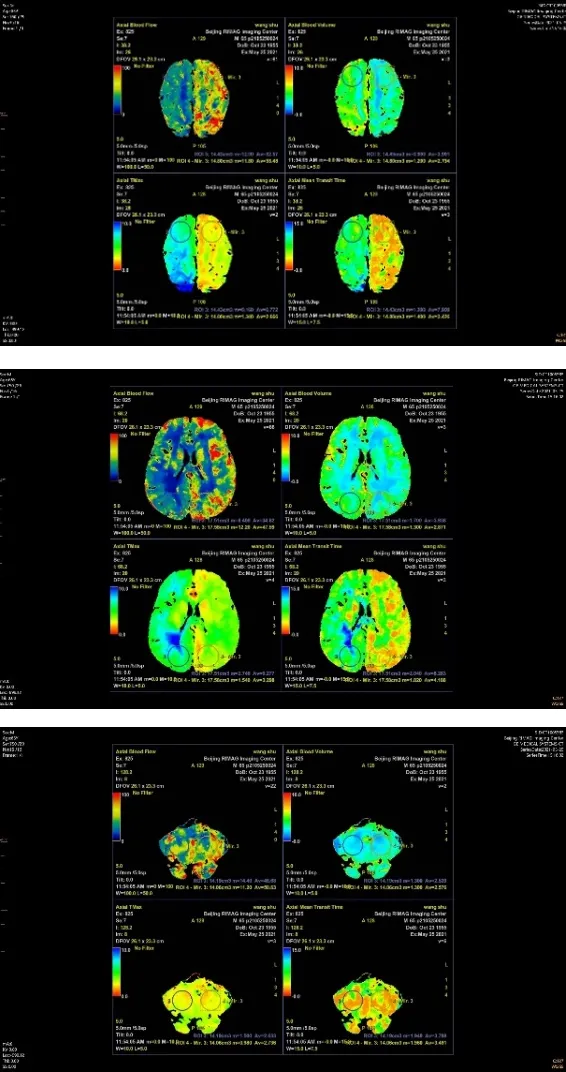

正常情況下,我們影像醫生和臨床醫生都普遍認為腦組織的血流灌注應該和供血動脈的狹窄程度呈正相關,也就是說供血動脈狹窄越重,其供血區腦組織血流灌注越差。在我們做過的幾十例病人的影像表現基本符合這種情況,即便有些不太一致的,我們多數情況下都認為是因為檢查敏感性差,屬於正常的偏差。近期有一位老年男性患者,65歲,高血壓病史多年,以頭暈就診,頭頸CTA示頸總動脈、頸內動脈、鎖骨下動脈、椎動脈廣泛輕中度狹窄,左側大腦中動脈M1段閉塞,遠側見側枝供血,右側大腦中動脈M1段中度狹窄,遠側動脈顯影尚可。頭顱CTP顯示右側額、頂、枕、顳普遍灌注減低,雙側小腦灌注大致對稱。頭顱CT平掃,雙側多發腔隙性梗死,右側病灶較多。寫這份報告時我們也覺得頭顱CTP的結果有些奇怪,於是我們查閱相關文獻並進行認真的討論,最後我們認為左側大腦中動脈閉塞是一個比較漫長的過程,遠側已經建立了完善的側枝迴圈,所以左側大腦中動脈供血區血流灌注並不低,而右側大腦中動脈M1段中度狹窄,因為未建立完善的側枝迴圈,所以其供血區血流灌注反而較低,這種減低真實反映了腦組織的灌注情況。

病例2:頭頸部CTA示頸總動脈、頸內動脈、鎖骨下動脈、椎動脈多發輕中度狹窄,左側大腦中動脈M1段閉塞,右側大腦中動脈M1段中度狹窄;頭顱CTP示右側額、頂、枕、顳廣泛灌注減低,雙側小腦灌注大致對稱。